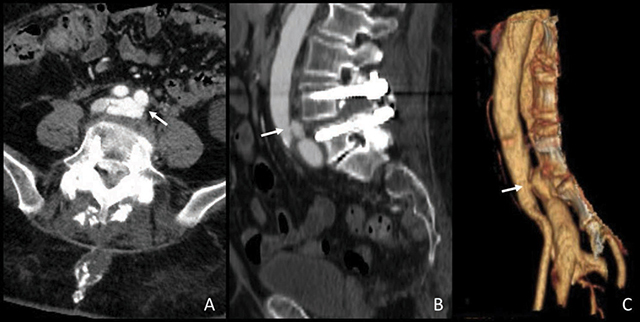

教学要点:虽然深静脉血栓是腰椎关节置换术后常见的并发症,但先天性动静脉瘘等罕见并发症也可能出现类似情况,这就凸显了广泛鉴别诊断和适当影像学检查对及时处理的重要性。

Teaching point: Although deep vein thrombosis is a common concern after lumbar arthrodesis, rare complications such as an iatrogenic arteriovenous fistula can present similarly, highlighting the importance of a broad, differential diagnosis and appropriate imaging for timely management.